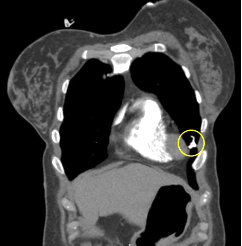

Công nghệ tim mạch Aheart

Phương pháp chỉnh sửa ECG

Hình ảnh lâm sàng